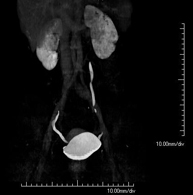

Prova diagnòstica que consisteix en obtenir imatges bi i tridimensionals del ronyó i del sistema urinari d'alta definició anatòmica mitjançant l'ús d'un equip de TC (Tomografia Computeritzada). Es realitza l'estudi abans i després de l'ús de contrast iodat en diferents "fases renals" per a una valoració funcional i anatòmica: parènquima renal, urèters, bufeta urinària, artèries i venes renals, etc. així com les estructures adjacents (vena cava inferior, aorta abdominal, fetge, melsa, etc.). Està especialment indicat quan hi ha sospita de lesions renals, en pacients amb sang a l'orina o hematúria, etc. - TC Urològic

Prova diagnòstica que consisteix en obtenir imatges bi i tridimensionals del ronyó i del sistema urinari d'alta definició anatòmica mitjançant l'ús d'un equip de TC (Tomografia Computeritzada). Està especialment indicat en aquells pacients en els quals se sospita que hi ha pedres al ronyó, infeccions urinàries de repetició. L'estudi es realitza sense utilitzar contrast iodat (només es casos determinats serà necessari completar l'estudi amb contrast iodat). - TC Pàncrees